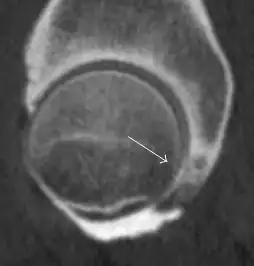

Figure 7:

-

Axial CT image of pigmented villonodular synovitis eroding the posterior cortex of the femoral neck.[1] -

Sagittal T2* gradient echo image showing a posterior soft tissue mass with hypointense areas secondary to hemosiderin deposition.[1] -

X-ray of synovial chondromatosis.[1] -

CT of synovial chondromatosis.[1]